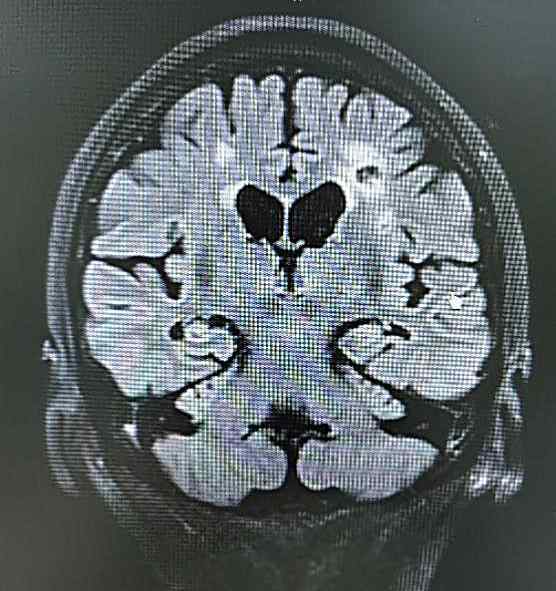

你看头颅MRI多发腔梗灶、严重脑白质变性就是我在王大爷脑子里“后院管理“的结果。

赵阿姨先有脑梗,出现“难伺候”、“疑心病”,就是我入驻了在赵阿姨脑子里,赵阿姨的诊断是脑梗后血管性痴呆,但记性变差,脑MRI显示海马有萎缩,是我携手夫君阿尔茨海默病共同造成的。